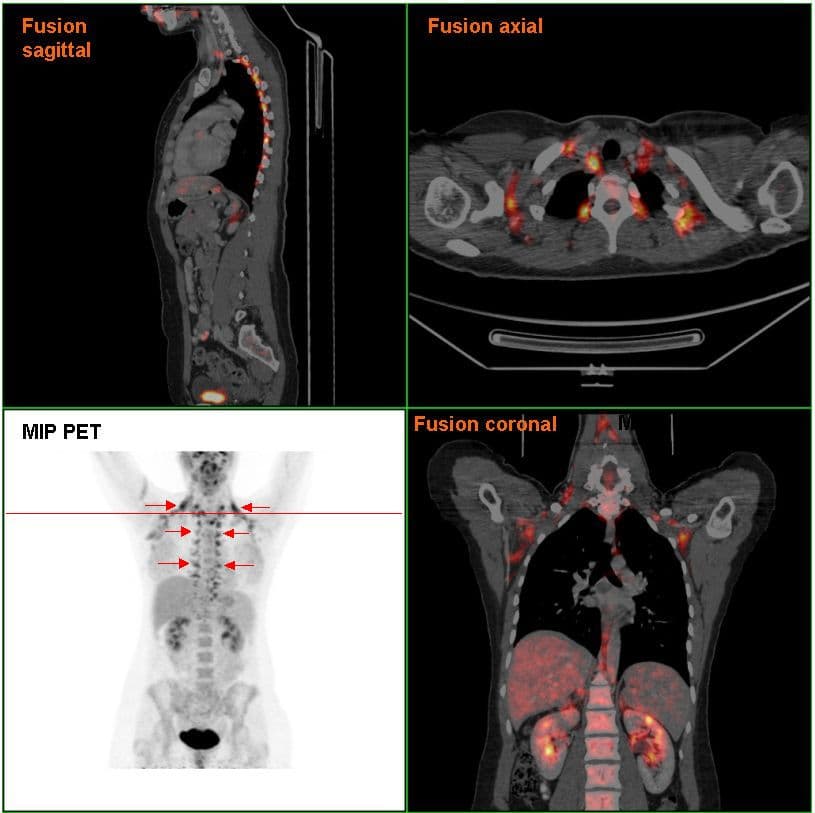

Brown adipose tissue (BAT) or brown fat makes up the adipose organ together with white adipose tissue (or white fat). Brown adipose tissue is found in almost all mammals. Classification of brown fat refers to two distinct cell populations with similar functions. The first shares a common embryological origin with muscle cells, found in larger "classic" deposits. The second develops from white adipocytes that are stimulated by the sympathetic nervous system. These adipocytes are found interspersed in white adipose tissue and are also named 'beige' or 'brite' (for "brown in white"). Brown adipose tissue is especially abundant in newborns and in hibernating mammals. It is also present and metabolically active in adult humans, but its prevalence decreases as humans age. Its primary function is thermoregulation. In addition to heat produced by shivering muscle, brown adipose tissue produces heat by non-shivering thermogenesis. The therapeutic targeting of brown fat for the treatment of human obesity is an active research field. In contrast to white adipocytes, which contain a single lipid droplet, brown adipocytes contain numerous smaller droplets and a much higher number of (iron-containing) mitochondria, which gives the tissue its color. Brown fat also contains more capillaries than white fat. These supply the tissue with oxygen and nutrients and distribute the produced heat throughout the body. The presence of brown adipose tissue in adult humans was discovered in 2003 during FDG-PET scans to detect metastatic cancers. Using these scans and data from human autopsies, several brown adipose tissue deposits have been identified. In infants, brown adipose tissue deposits include, but are not limited to: interscapular, supraclavicular, suprarenal, pericardial, para-aortic and around the pancreas, kidney and trachea. These deposits gradually get more white fat-like during adulthood. In adults, the deposits that are most often detected in FDG-PET scans are the supraclavicular, paravertebral, mediastinal, para-aortic and suprarenal ones.